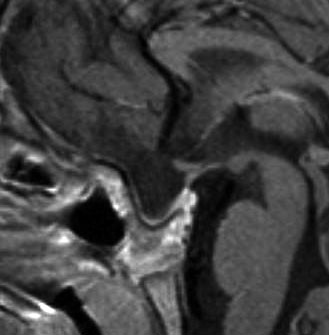

9歳児の頭蓋咽頭腫です。視力障害が高度なので鼻の孔(経蝶形骨洞手術)から急いで全摘出しました。腫瘍の塊がトルコ鞍の底にありますが,この部分は開頭手術では多少見づらいです。術後に視力は少し良くなりました。1年後のMRI(右側)では下垂体組織は残っていて,前葉ホルモンは正常ですが軽い尿崩症があります。